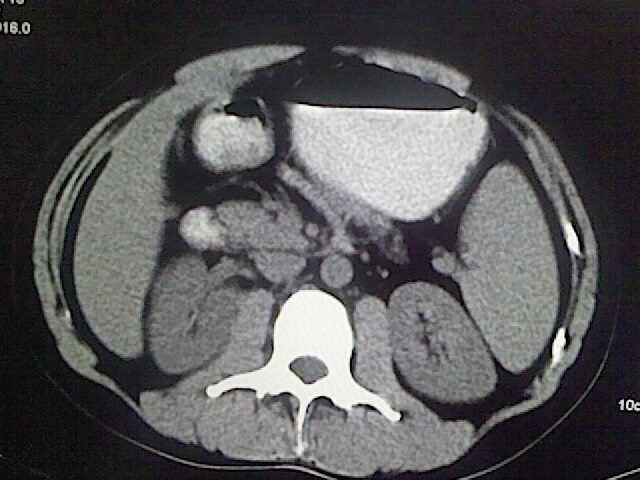

以下是引用卜一在2009-3-14 9:49:00的发言:[br]胆囊萎缩,胆囊壁不规则增厚,内部结构模糊,增强明显强化。另:肝左叶外侧段肝囊肿。支持:慢性胆囊炎!高度可疑:胆囊癌!

以下是引用余辉在2009-3-14 8:48:00的发言:[br]1)慢性胆囊炎。2)肝左叶外侧段肝囊肿。3)脂肪肝。[br]支持,胆囊萎缩,密度增高,不知b超具体有何提示,钙胆汁?结石?

以下是引用jiangjing在2009-3-14 10:18:00的发言:[br]1)慢性胆囊炎。2)肝左叶外侧段肝囊肿。3)脂肪肝。4.】建议行肝功能检查